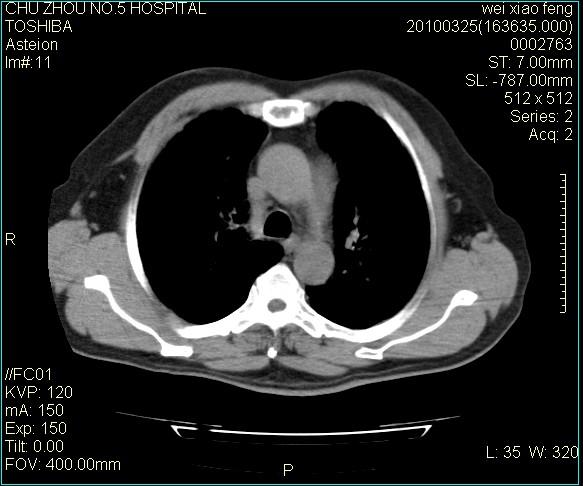

男,60岁,反复咳、痰、喘3月,加重3天。

双肺间质性改变。

考虑双肺血型潘散肺结核/

间质性肺炎伴间质纤维化!不排除伴有职业病!

双肺间质纤维化,双肺血型潘散肺结核。

考虑间质性肺炎伴间质纤维化。

右肺中叶结节影为原发灶,考虑右肺中叶周围型肺癌并淋巴道转移